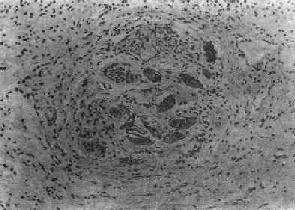

图19-5 肝血吸虫病之急性虫卵结节 结节中心有一成熟虫卵,卵壳表面可见放射状物质,周围广泛坏死伴大量嗜酸性粒细胞浸润

第二节 血吸虫病血吸虫病(schistosomiasis)是由血吸虫寄生于人体引起的地方性寄生虫病。寄生于人体的血吸虫主要有三种:即流行于非洲北部的埃及血吸虫(Schistosoma haematobium);流行于拉丁美洲及非洲中部的曼氏血吸虫(Schistosoma mansoni)以及流行于亚洲的日本血吸虫(Schistosoma japanicum)。在我国因只有日本血吸虫病流行,故通常将日本血吸虫病简称为血吸虫病。 根据1972年在湖南长沙马王堆一号墓出土的西汉女尸及1975年在湖北江陵出土的西汉男尸内皆发现有大量典型血吸虫卵的事实,证明在2100多年前我国已有血吸虫病的流行。本病在我国主要流行于长江流域及其以南的十三个省市的广大水稻作物地区,尤以江苏、浙江、安徽、湖北、湖南、江西等省及上海市效较为严重。过去本病流行猖獗,对广大劳动人民的健康危害极大。新中国成立后,积极发展了防治工作,广东、广西、福建、江苏和上海等五个省市和全国270多个县已基本消灭了血吸虫病。 【病因及感染途径】 日本血吸虫的生活史可分为虫卵、毛蚴、胞蚴、尾蚴、童虫及成虫等阶段。成虫以人体或其他哺乳动物如狗、猫、猪、牛及马等为终宿主,自毛蚴至尾蚴的发育繁殖阶段以钉螺为中间宿主。 血吸虫虫卵随同病人或病畜的粪便排入水中,卵内的毛蚴成熟孵化,破壳而出,以后钻入钉螺体内,经过母胞蚴及子胞蚴阶段后,大量尾蚴发育成熟,并游动于水中。当人畜与疫水接触时,尾蚴借其头腺分泌的溶组织酶作用和其肌肉收缩的机械运动,很快钻入皮肤(或粘膜)并脱去尾部变为童虫。童虫经小静脉或淋巴管进入血液循环,再经右心而到达肺。以后由肺的毛细血管经肺静脉而入大循环向全身散布。只有进入肠系膜静脉的童虫,才能继续发育为成虫,其余多在途中夭折。通常在感染尾蚴后3周左右即可发育为成虫,雌雄成虫交配后即可产卵。虫卵随门静脉血流顺流到肝,或逆流入肠壁而沉着在组织内,约经11天左右逐渐发育为成熟虫卵,内含毛蚴。肠壁内的虫卵可破坏肠粘膜而进入肠腔,并随粪便排出体外,再重演生活周期。虫卵在组织内的寿命约为21天左右。雌雄合抱的成虫在人体内的寿命一般为3~4年。 【病变和发病机制】 血吸虫发育阶段中的尾蚴、童虫及成虫、虫卵等均可引起病变,但以虫卵引起的病变最严重,危害也最大。 1.尾蚴及童虫引起的病变 (1)尾蚴性皮炎:尾蚴侵入皮肤后,可引起皮肤的炎症反应,称为尾蚴性皮炎(cercarial dermatitis)。多发生于重复感染的患者,一般在尾蚴钻入皮肤后数小时至2~3日内发生,表现为红色小丘疹,奇痒,经数日后可自然消退。镜下见真皮充血、出血及水肿,起初有中性及嗜酸性粒细胞浸润,以后主要为密集的单核细胞浸润。 目前认为本病的发病机制主要与迟发性变态反应有关。动物实验证明,转移感染小鼠的淋巴细胞给正常小鼠,再接种尾蚴,经1~2天,局部童虫周围有单核细胞浸润。在反应早期可能有抗体介导的免疫反应参与。 (2)肺部病变:童虫移行到肺时,部分可穿破肺泡壁毛细血管,游出到肺组织中,引起点状出血及白细胞浸润(约在感染后1~2天)并可有血管炎改变,但病变一般轻微而短暂。 童虫经大循环移行到其他器官时也可引起与肺类似的改变。 童虫所引起的各器官点状出血除与童虫的机械作用有关外,还与其代谢产物或虫体死亡后蛋白分解产物所致人体组织的变态反应有关。 宿主感染血吸虫后得到获得性免疫,对再感染产生不同程度的抵抗力。其机制为抗体依赖、细胞介导的细胞毒反应,由IgE或IgG2a抗体,巨噬细胞、嗜酸性粒细胞等参与。主要作用于表面有抗原表达的幼龄童虫,嗜酸性粒细胞有IgG和IgE的Fc受体,当抗体包被童虫后其Fc段与Fc受体结合,并使嗜酸性粒细胞粘附在童虫表面且脱颗粒,释出细胞毒性物质,而起杀伤作用。巨噬细胞也是非常重要的效应细胞。 2.成虫引起的病变 血吸虫在门静脉系统内发育成熟后,其代谢产物可使机体发生贫血、嗜酸性粒细胞增多、脾肿大、静脉内膜炎及静脉周围炎等。在肝、脾的单核吞噬细胞系统的细胞内,常见有黑褐色血吸虫色素沉着,是成虫吞食红细胞后,在虫体内珠蛋白酶作用下,使血红蛋白分解而形成的一种血红素样色素,同样的色素也见于成虫的肠道内。活的成虫本身在静脉内不引起宿主反应,其解释是成虫的表膜内含有宿主的抗原,被宿主认为是“自我”组织而逃避了免疫攻击。成虫死亡后,多在肝内分解,产生毒性,可引起明显的静脉炎和静脉周围炎。死亡虫体周围组织坏死,大量嗜酸性粒细胞浸润,形成嗜酸性脓肿,与血丝虫成虫死亡后引起的变化相似。 3.虫卵引起的变化 虫卵沉着所引起的损害是最主要的病变,虫卵除主要沉着于乙状结肠和直肠壁以及肝外,也常见于回肠末段、阑尾及升结肠等处。肺、脑等其他器官有时也可见到。未成熟的虫卵所引起的病变轻微;含毛蚴的成熟虫卵往往引起虫卵结节形成。按其病变发展过程可分为急性虫卵结节和慢性虫卵结节两种。 (1)急性虫卵结节:肉眼观为灰黄色、粟粒至绿豆大(0.5~4mm)的小结节。镜下见结节中央常有1~2个成熟虫卵,也偶可多达20个以上。这些成熟虫卵的卵壳上附有放射状嗜酸性的棒状体,也称为Hoeppli现象,用免疫荧光法已证实为抗原抗体复合物。虫卵周围是一片无结构的颗粒状坏死物质及大量嗜酸性粒细胞浸润。因其病变类似脓肿,故也称为嗜酸性脓肿(图19-5)。在坏死组织中可混杂多数菱形或多面形屈光性蛋白质晶体,即Charcot-Leyden结晶,系嗜酸性粒细胞的嗜酸性颗粒互相融合而成。随后虫卵周围产生肉芽组织层,其中有以嗜酸性粒细胞为主的炎症细胞浸润,还有单核巨噬细胞、淋巴细胞、浆细胞及少量中性粒细胞。随着病程的发展,肉芽组织层逐渐向虫卵结节中央生长,并出现围绕结节呈放射状排列的类上皮细胞层。类上皮细胞层逐渐加宽,嗜酸性粒细胞显著减少,构成晚期急性虫卵结节(图19-6),这是向慢性虫卵结节发展的过渡阶段。